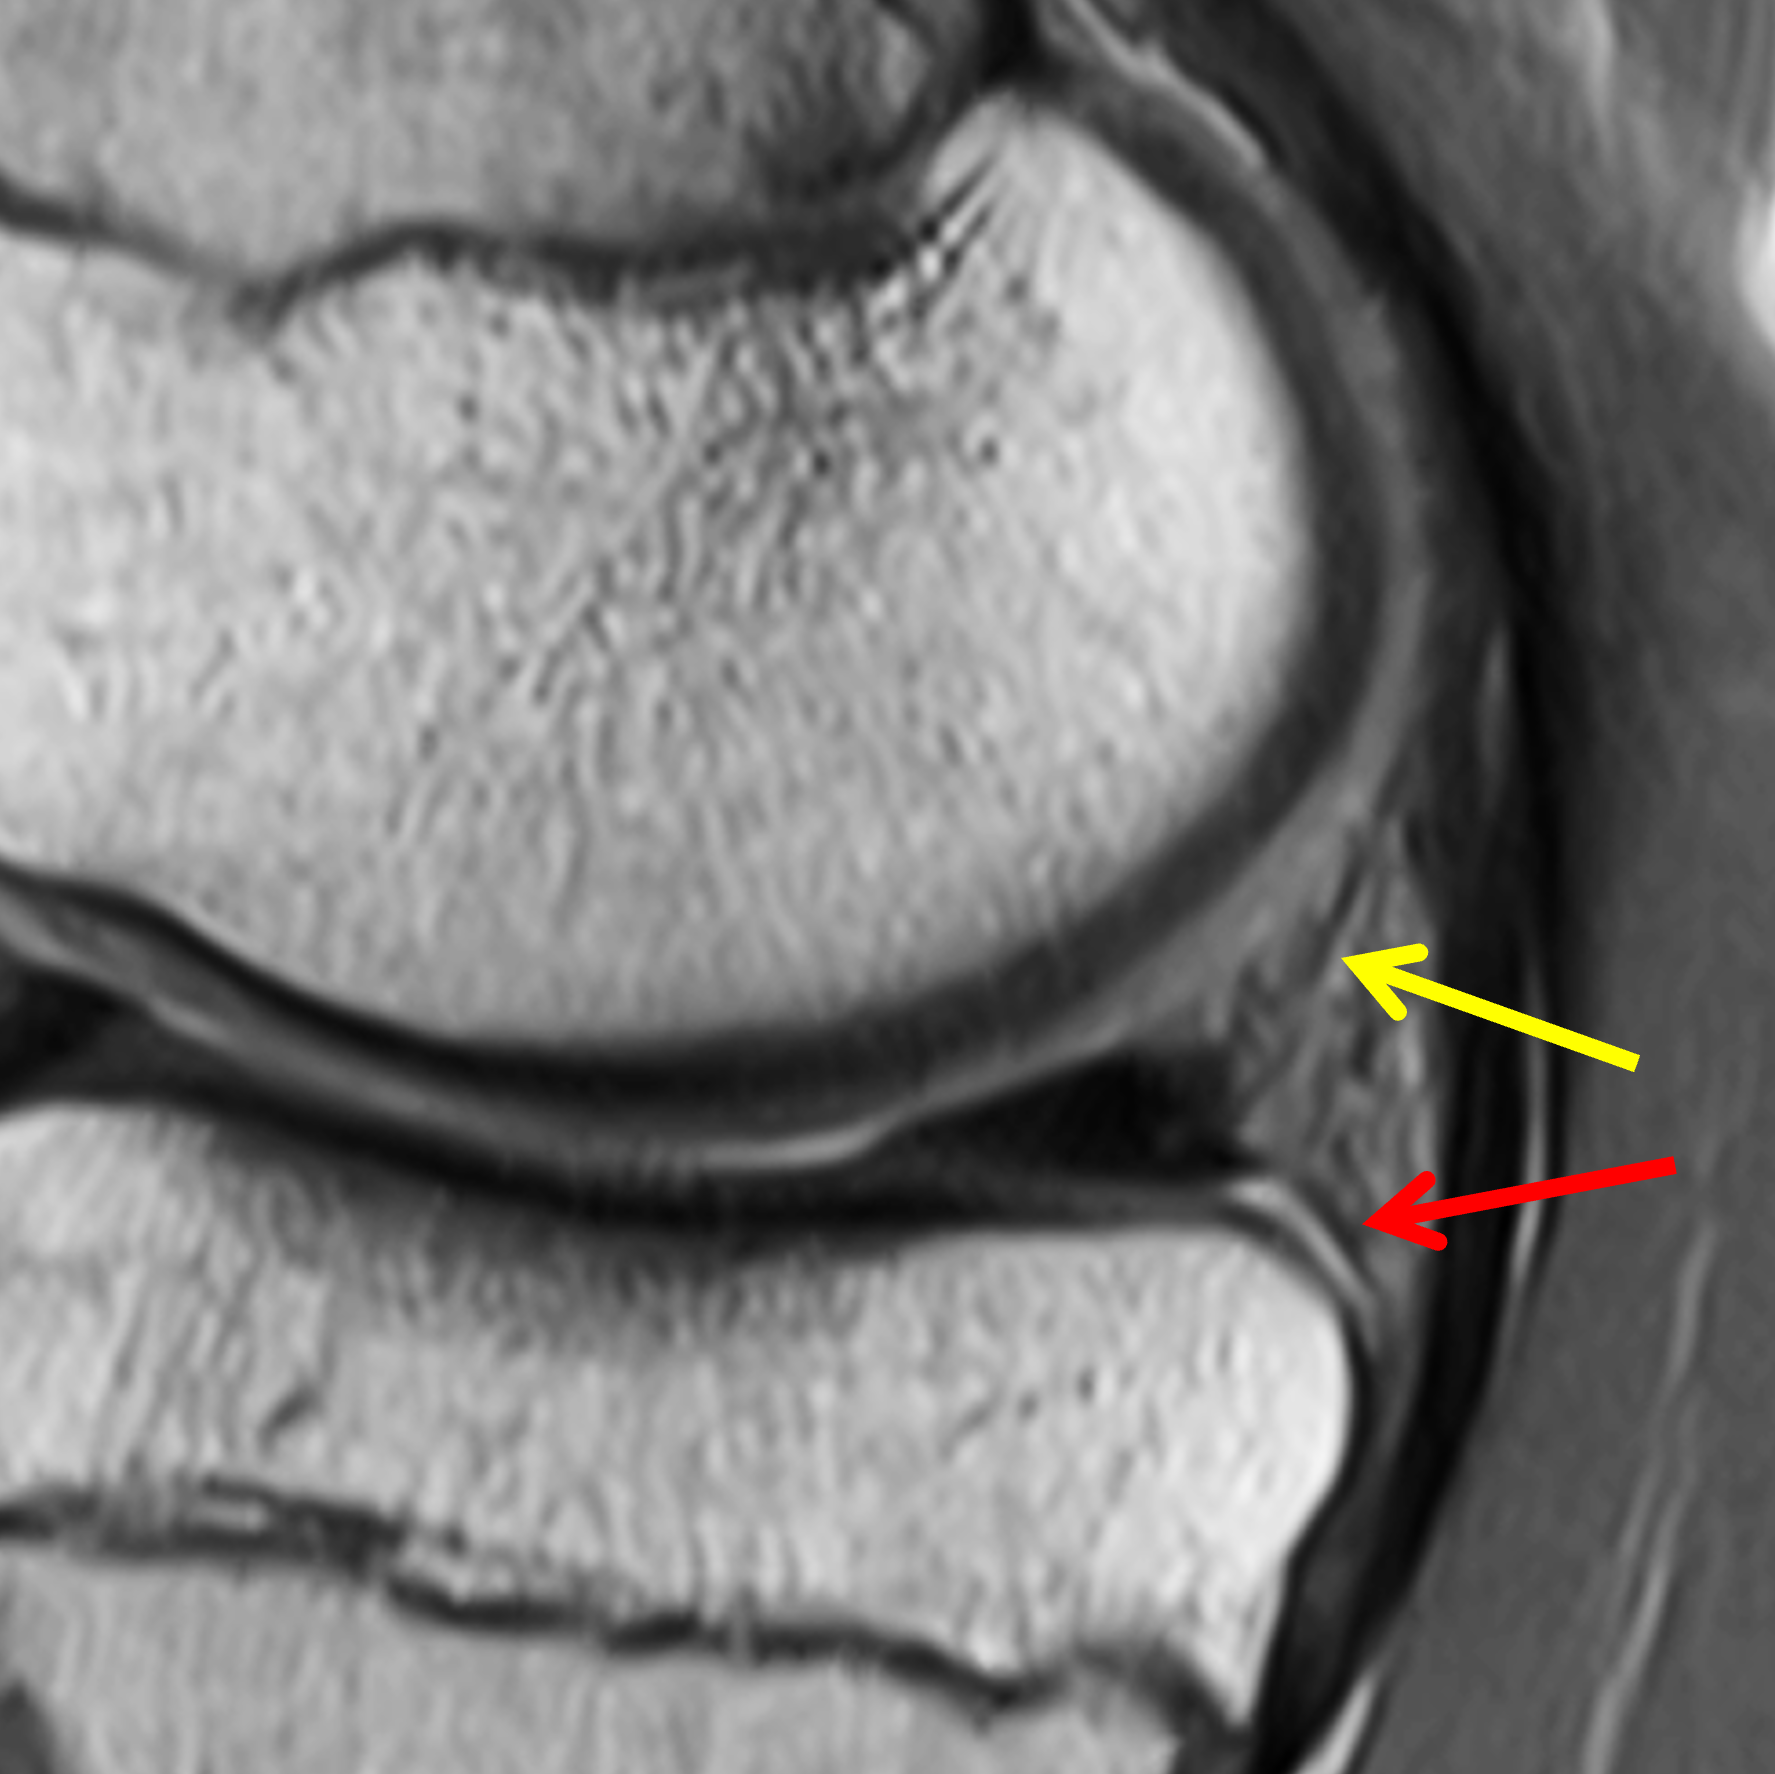

The meniscocapsular and meniscotibial ligaments both arise from the posterior margin of the PHMM (Figures 3 and 4). The meniscocapsular ligament courses posterosuperiorly and blends into the capsule with a variable amount of meniscosynovial tissue covering its superior articular surface. The meniscotibial ligament travels posteroinferiorly and anchors to the posterior tibia several millimeters below the articular surface. The ligaments are comprised of type 1 collagen but are less compacted than typical ligamentous structures, with loose adipose and vascular tissue interposed between the two ligaments.8,21

Figure 4: Normal MRI anatomy of the posteromedial knee. (4A) Sagittal proton density-weighted image shows the meniscocapsular ligament (yellow arrow) and the meniscotibial ligament (red arrow) attached to the posterior horn of the medial meniscus. (4B) Fat-suppressed fluid-sensitive image demonstrates loose connective and adipose tissue (asterisk), which is hyperintense due to its inherent vascularity, between the posterior ligaments. Note the meniscotibial ligament insertion on the tibia several millimeters below the articular cartilage (arrowhead).